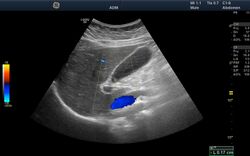

Ultrasound image showing the liver, gallbladder and common bile duct.

Medical ultrasound uses high frequency broadband sound waves in the megahertz range that are reflected by tissue to varying degrees to produce (up to 3D) images. This is commonly associated with imaging the fetus in pregnant women. Uses of ultrasound are much broader, however. Other important uses include imaging the abdominal organs, heart, breast, muscles, tendons, arteries and veins. While it may provide less anatomical detail than techniques such as CT or MRI, it has several advantages which make it ideal in numerous situations, in particular that it studies the function of moving structures in real-time, emits no ionizing radiation, and contains speckle that can be used in elastography. Ultrasound is also used as a popular research tool for capturing raw data, that can be made available through an ultrasound research interface, for the purpose of tissue characterization and implementation of new image processing techniques. The concepts of ultrasound differ from other medical imaging modalities in the fact that it is operated by the transmission and receipt of sound waves. The high frequency sound waves are sent into the tissue and depending on the composition of the different tissues; the signal will be attenuated and returned at separate intervals. A path of reflected sound waves in a multilayered structure can be defined by an input acoustic impedance (ultrasound sound wave) and the Reflection and transmission coefficients of the relative structures.[13] It is very safe to use and does not appear to cause any adverse effects. It is also relatively inexpensive and quick to perform. Ultrasound scanners can be taken to critically ill patients in intensive care units, avoiding the danger caused while moving the patient to the radiology department. The real-time moving image obtained can be used to guide drainage and biopsy procedures. Doppler capabilities on modern scanners allow the blood flow in arteries and veins to be assessed.

Creation of three-dimensional images